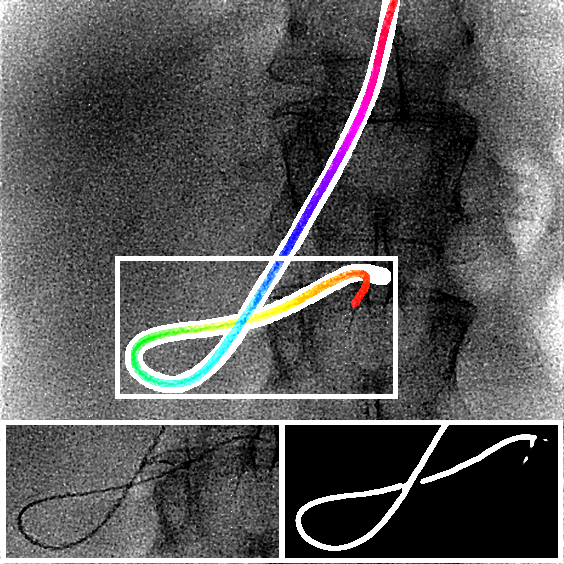

The output of the neural network is first thresholded with a threshold (between 0 and 1) and then skeletonized [19]. Next, the branches (ordered sets of pixels) are determined based on connectivity. Connection points are created between close branches. If the closest points between two branches are within a distance pixels, we consider this to be a possible connection, and there can be only one connection between two particular branches. Then, to link the branches, three steps are done (Fig. 2). First, for each connection, we divide and merge branches in order to have the longest branches. Second, loops are detected and merged following the direction at the crossing point. We have a loop in a branch when two points, within a distance pixels, have their distance along the branch of at least pixels. Before the third step, the first and second steps are repeated a second time with a distance superior to . Finally, in the last step, the remaining connected branches larger than pixels are considered as incomplete loops or straight loops due to foreshortening. We process them similarly as the second step by closing the two endpoints of their branch. When all the potential links have been processed, we keep the longest connected set of branches and choose amongst the two endpoints the farthest from the image border as the tip of the catheter centerline. Finally, the centerline is smoothed by fitting a spline.

We evaluate using the tip distance error (i.e. the distance between the annotated catheter tip and the tip of the segmented catheter), and the average distance between the manually segmented catheter and the automatically segmented catheter. Figure 3 shows the tip and catheter distances results. We compute the precision of the tip between consecutive frames. The median, average, minimum and maximum of the standard deviation per sequence of the tip distance error are respectively 0.7 mm, 4.9 mm, 0.1 mm and 55.7 mm. Five examples of segmentation are shown in Figure 4. In the third frame, the segmentation is going too far and follows part of the vertebrae. The fourth frame misses the proximal part of the catheter. The last frame is the only sequence with significant false positives. It is less noisy because it has been acquired with higher radiation dose. The neural network was not trained for such sequence.

Very few images have false positives after the CNN segmentation. Therefore, we can use simple criteria to extract the catheter centerline from the CNN segmentation. The results show that it works well and can handle self-intersections. The main problem in the extracted catheters are sometimes large gaps in the segmentation due to false negatives. As a consequence, occasionally the proximal part of the catheter is missing. With a larger training set, the model is expected to generalize better.